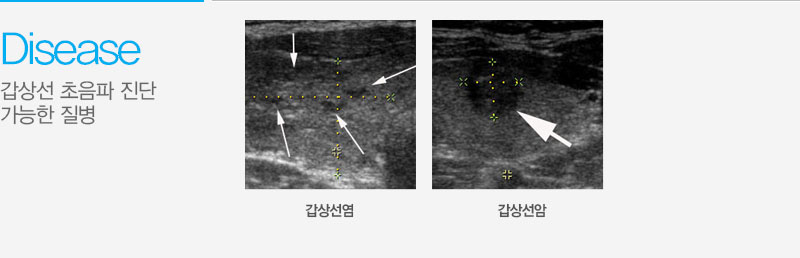

갑상선 초음파